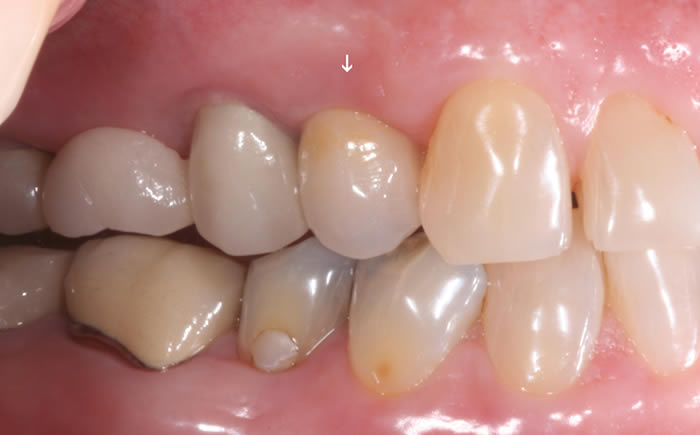

More back teeth replaced by dental implants

Case Three (2 images)

Case Four (4 images)

Case Five (4 images)

Case Six (8 images)

Case Seven (4 images)